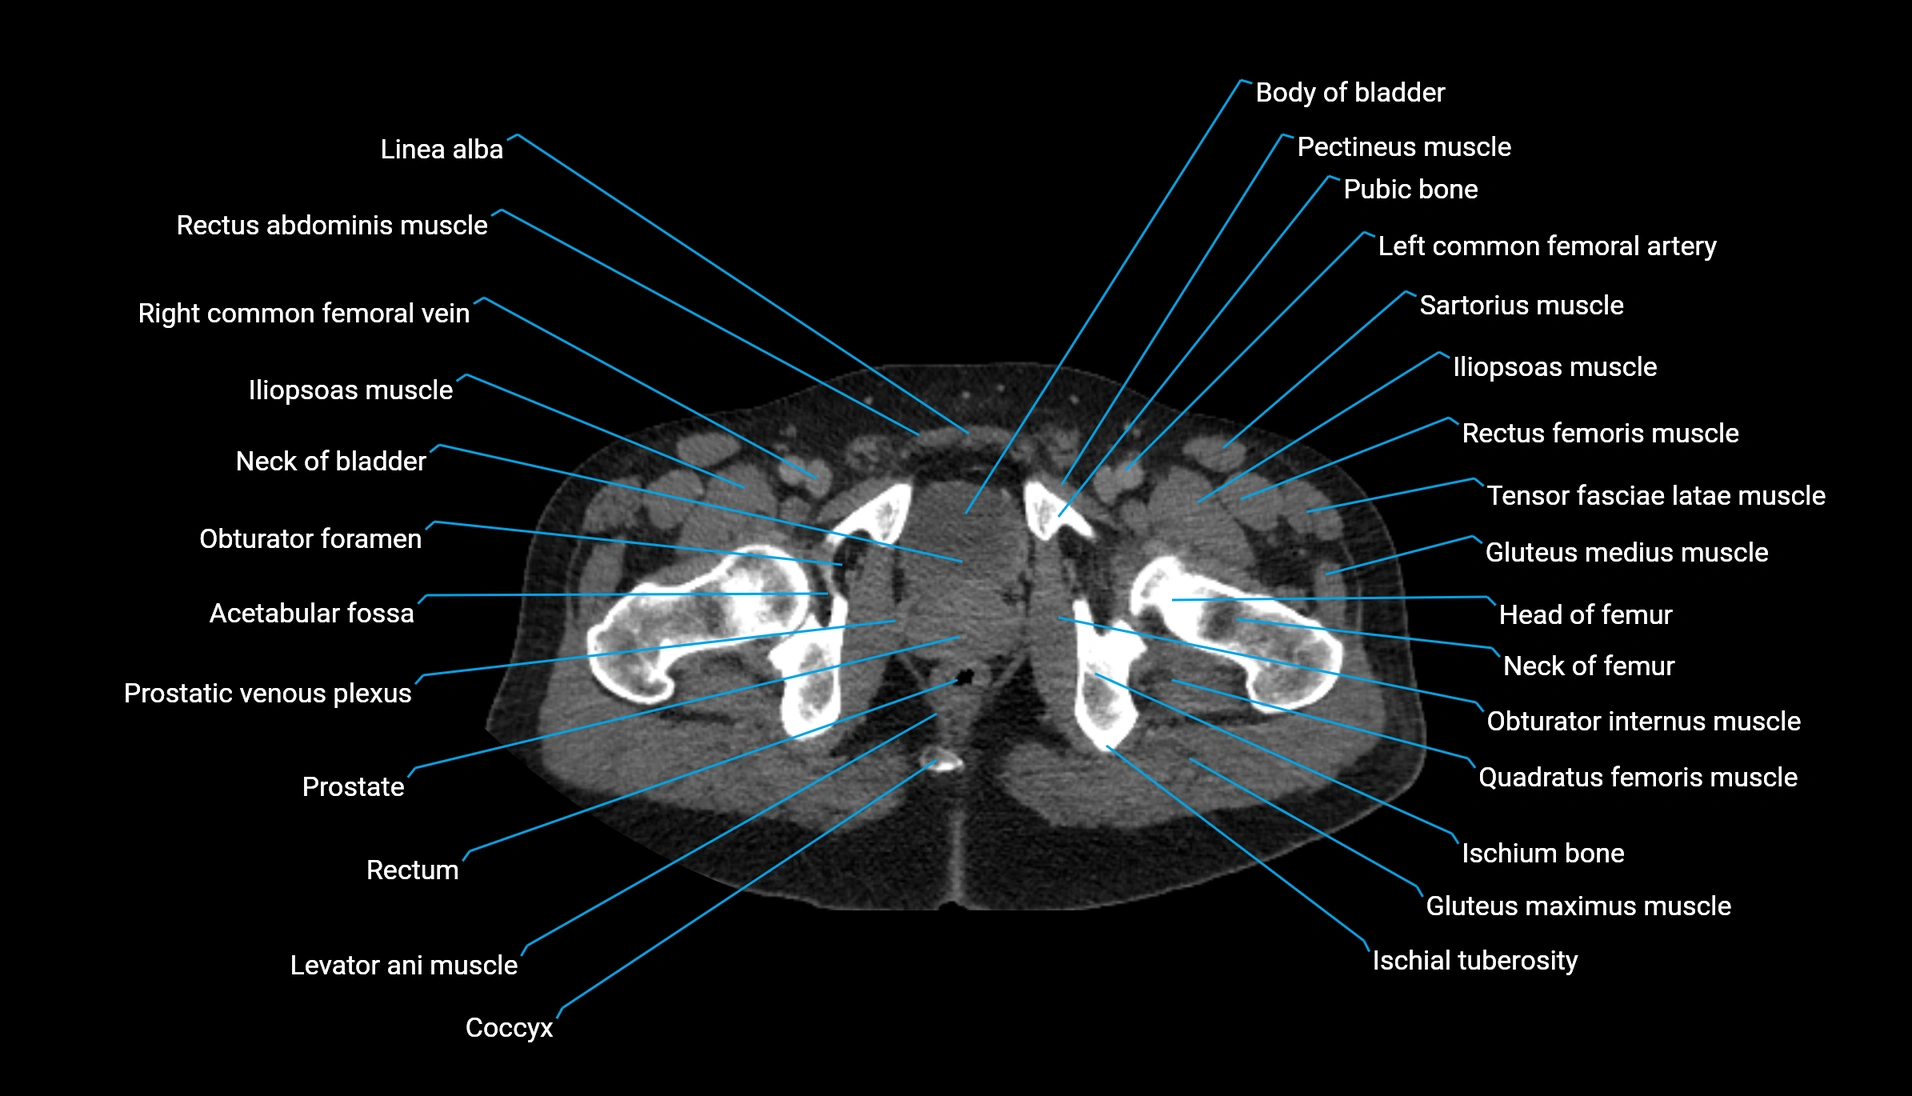

CT Appearance

Non-contrast CT:

-

Demonstrates cortical bone of acetabular rim in excellent detail

Detects fractures, dysplasia, retroversion, or bony overcoverage (pincer impingement)

3D reconstructions used in preoperative hip surgery planning

CT VRT 3D image

CT image